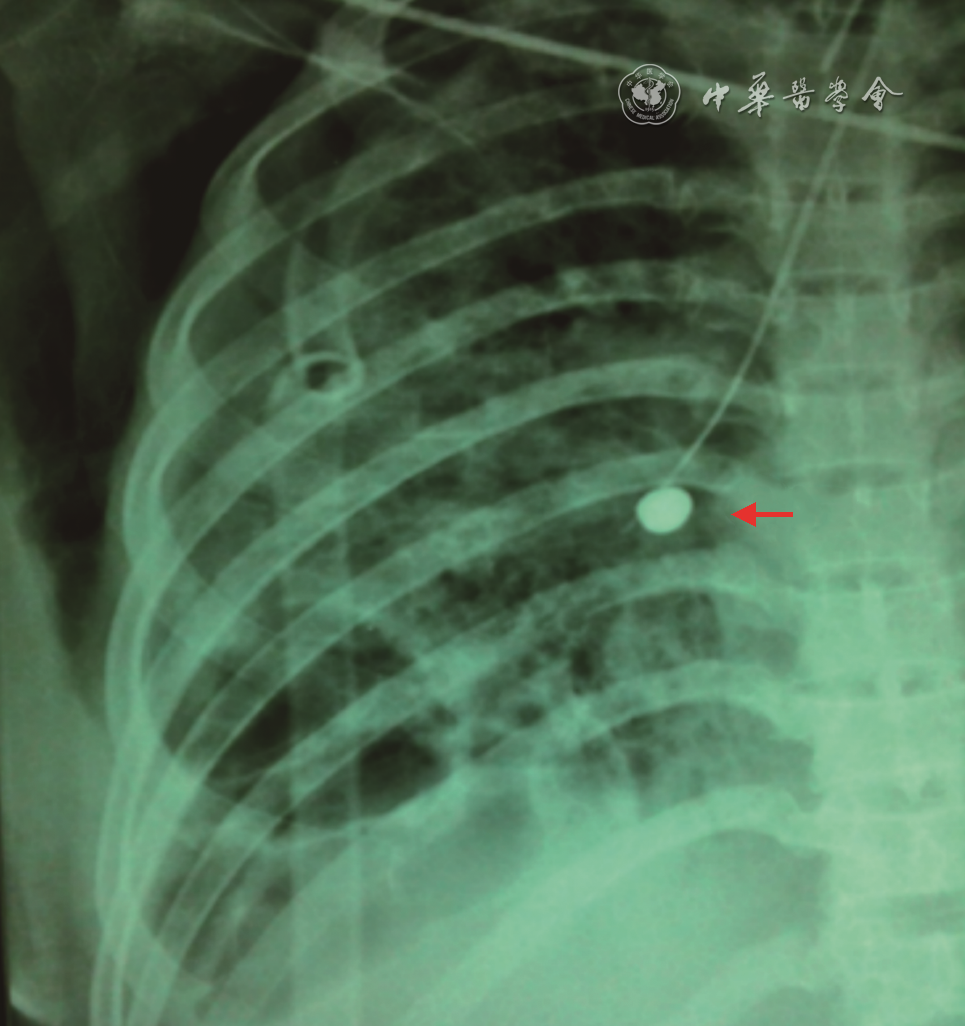

(3)球囊导管填塞:1)材料:球囊导管填塞主要用于机械通气并发难治性气胸,可起到保证有效通气量及促进破裂口愈合的作用。机械通气合并气胸在急性呼吸衰竭中提示预后不良,其病死率为50%~67%,机械通气合并难治性气胸使用封堵剂对责任引流支气管进行封堵不太恰当,这主要是由于封堵剂很难立刻被取出或清除,如果发生因封堵剂堵塞肺组织而导致通气及换气功能恶化则无法使被封堵的肺叶肺段马上恢复通气。而使用球囊导管填塞漏气支气管则法符合随时撤销封堵的要求,放置过程亦无需中断机械通气,这对于存在心肺功能不全的老年患者尤为重要(图6)。2)技术流程:①确定目标支气管:送入支气管镜,如患者正在进行机械通气,则可将气管导管球囊适量放气以便支气管镜从球囊边通过。探查方法按前述步骤进行;②放置导丝:确定目标支气管后,退出球囊导管,经支气管镜工作通道将导丝送入目标支气管,接着退出支气管镜;③沿导丝将球囊导管送入目标支气管,并再次进镜确保球囊位置正确,向球囊中注入水溶性碘造影剂充盈球囊(可在X线下显影)使之填塞目标支气管,观察引流瓶中气体引流情况;④注意事项:球囊导管填塞成功后可行床旁X线胸片,确定球囊位置以备治疗过程中复查时对照。当球囊导管填塞目标支气管后应当继续留下置导丝,并使导丝从导管先端部向目标支气管远端伸出3~4 cm,以防止在咳嗽时球囊导管被弹出移位。3)疗效及并发症:1982年Ellis等报道了1例采用球囊导管填塞治疗机械通气并发难治性气胸取得成功的病例。机械通气并发气胸使有效通气量的维持变得困难、使通气/血流变得进一步失调,这是一种高危状态。而Ellis的经验为这一棘手的难题提供了一种值得尝试的解决途径。当然近年来随着肺减容活瓣及支气管塞在难治性气胸的成功应用,采用这两种封堵器治疗机械通气并发气胸应该可行且有效。

c4277a3f5fc5be9f04510241f63e9f16.png

图6 X线胸片示球囊导管填塞治疗机械通气合并难治性气胸,红色箭头所指为注入造影剂后的球囊